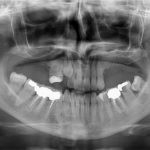

Il ricorso alla tecnologia digitale trova sempre maggiori indicazioni in campo progettuale per riabilitazioni estese di intere arcate dentarie o per il posizionamento di un singolo impianto in zone. Il caso clinico presentato è stato trattato con pianificazione guidata e successivo inserimento implantare con dima chirurgica dedicata

Vengono descritte le procedure chirurgiche e protesiche per la realizzazione di una riabilitazione full-arch mandibolare fissa su quattro impianti mediante pianificazione computer-guidata del caso,...